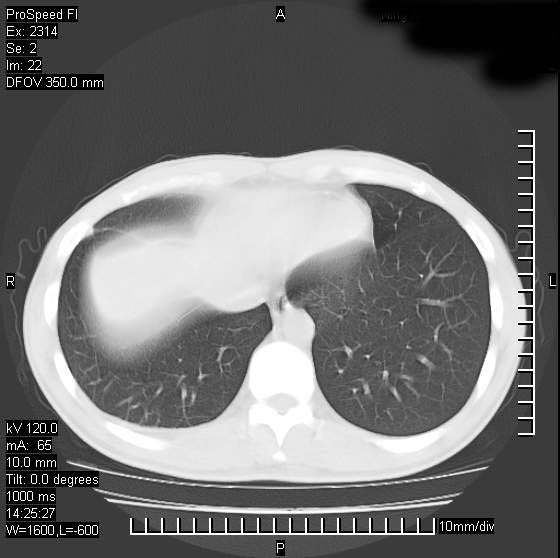

男性,再生障碍性贫血,入院前发热10天,最高40c,右侧胸痛,外院ct示右上,中肺边缘模糊的球性影(就是我现在图中标示的范围),考虑炎症,在我院使用头孢呋辛,洛美沙星10天,高烧消退,自感下午稍有发热,但今天ct示右上,中肺病灶明显扩大,还是考虑炎症,看其中的球型影是否霉菌感染??,是否能排除结核?

右肺中叶外侧段病变,上缘界限不清,下缘锐利,以段性发病为主,内见巨大空洞及空洞内容物,结合病史首先考虑:化脓性肺炎。不除外霉菌感染!

片状高密度影内见空洞影,内可见球形软组织密度影,并有新月征,考虑霉菌感染.

支持右肺上叶、中叶外侧段节段性肺炎伴脓肿形成。